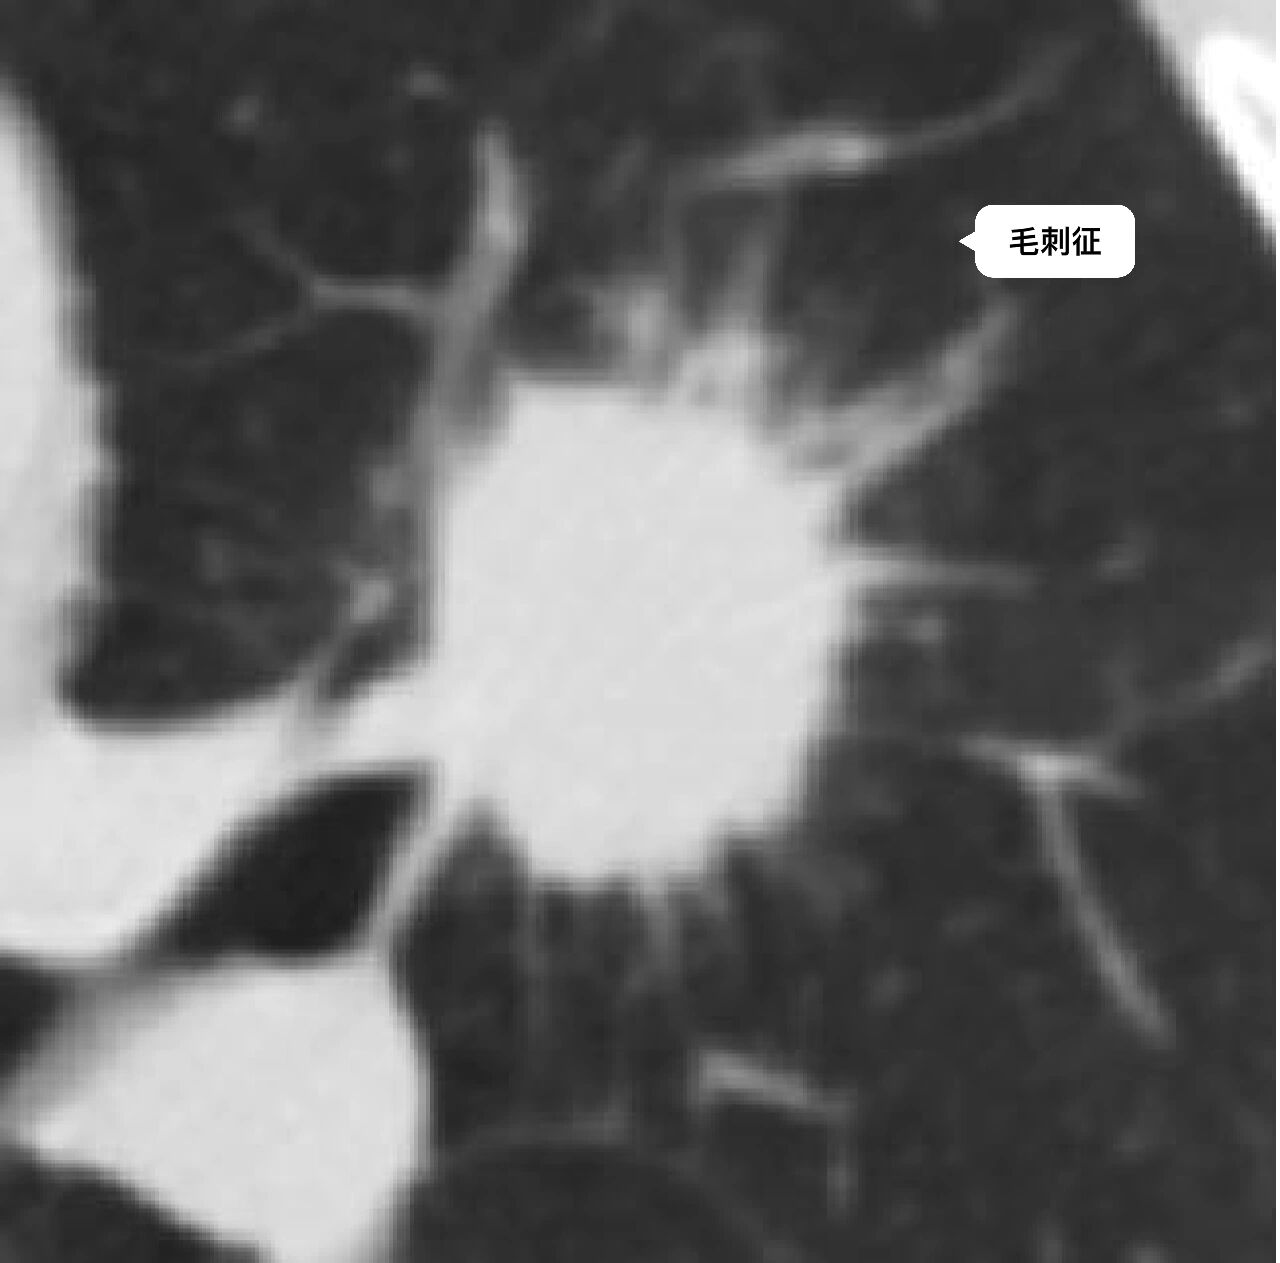

分叶征 毛刺征

周围型肺癌征象之分叶征,毛刺征,棘状突起

毛刺形成机制:肿瘤组织中含有向内收缩的纤维组织,致使肿瘤边缘出现较